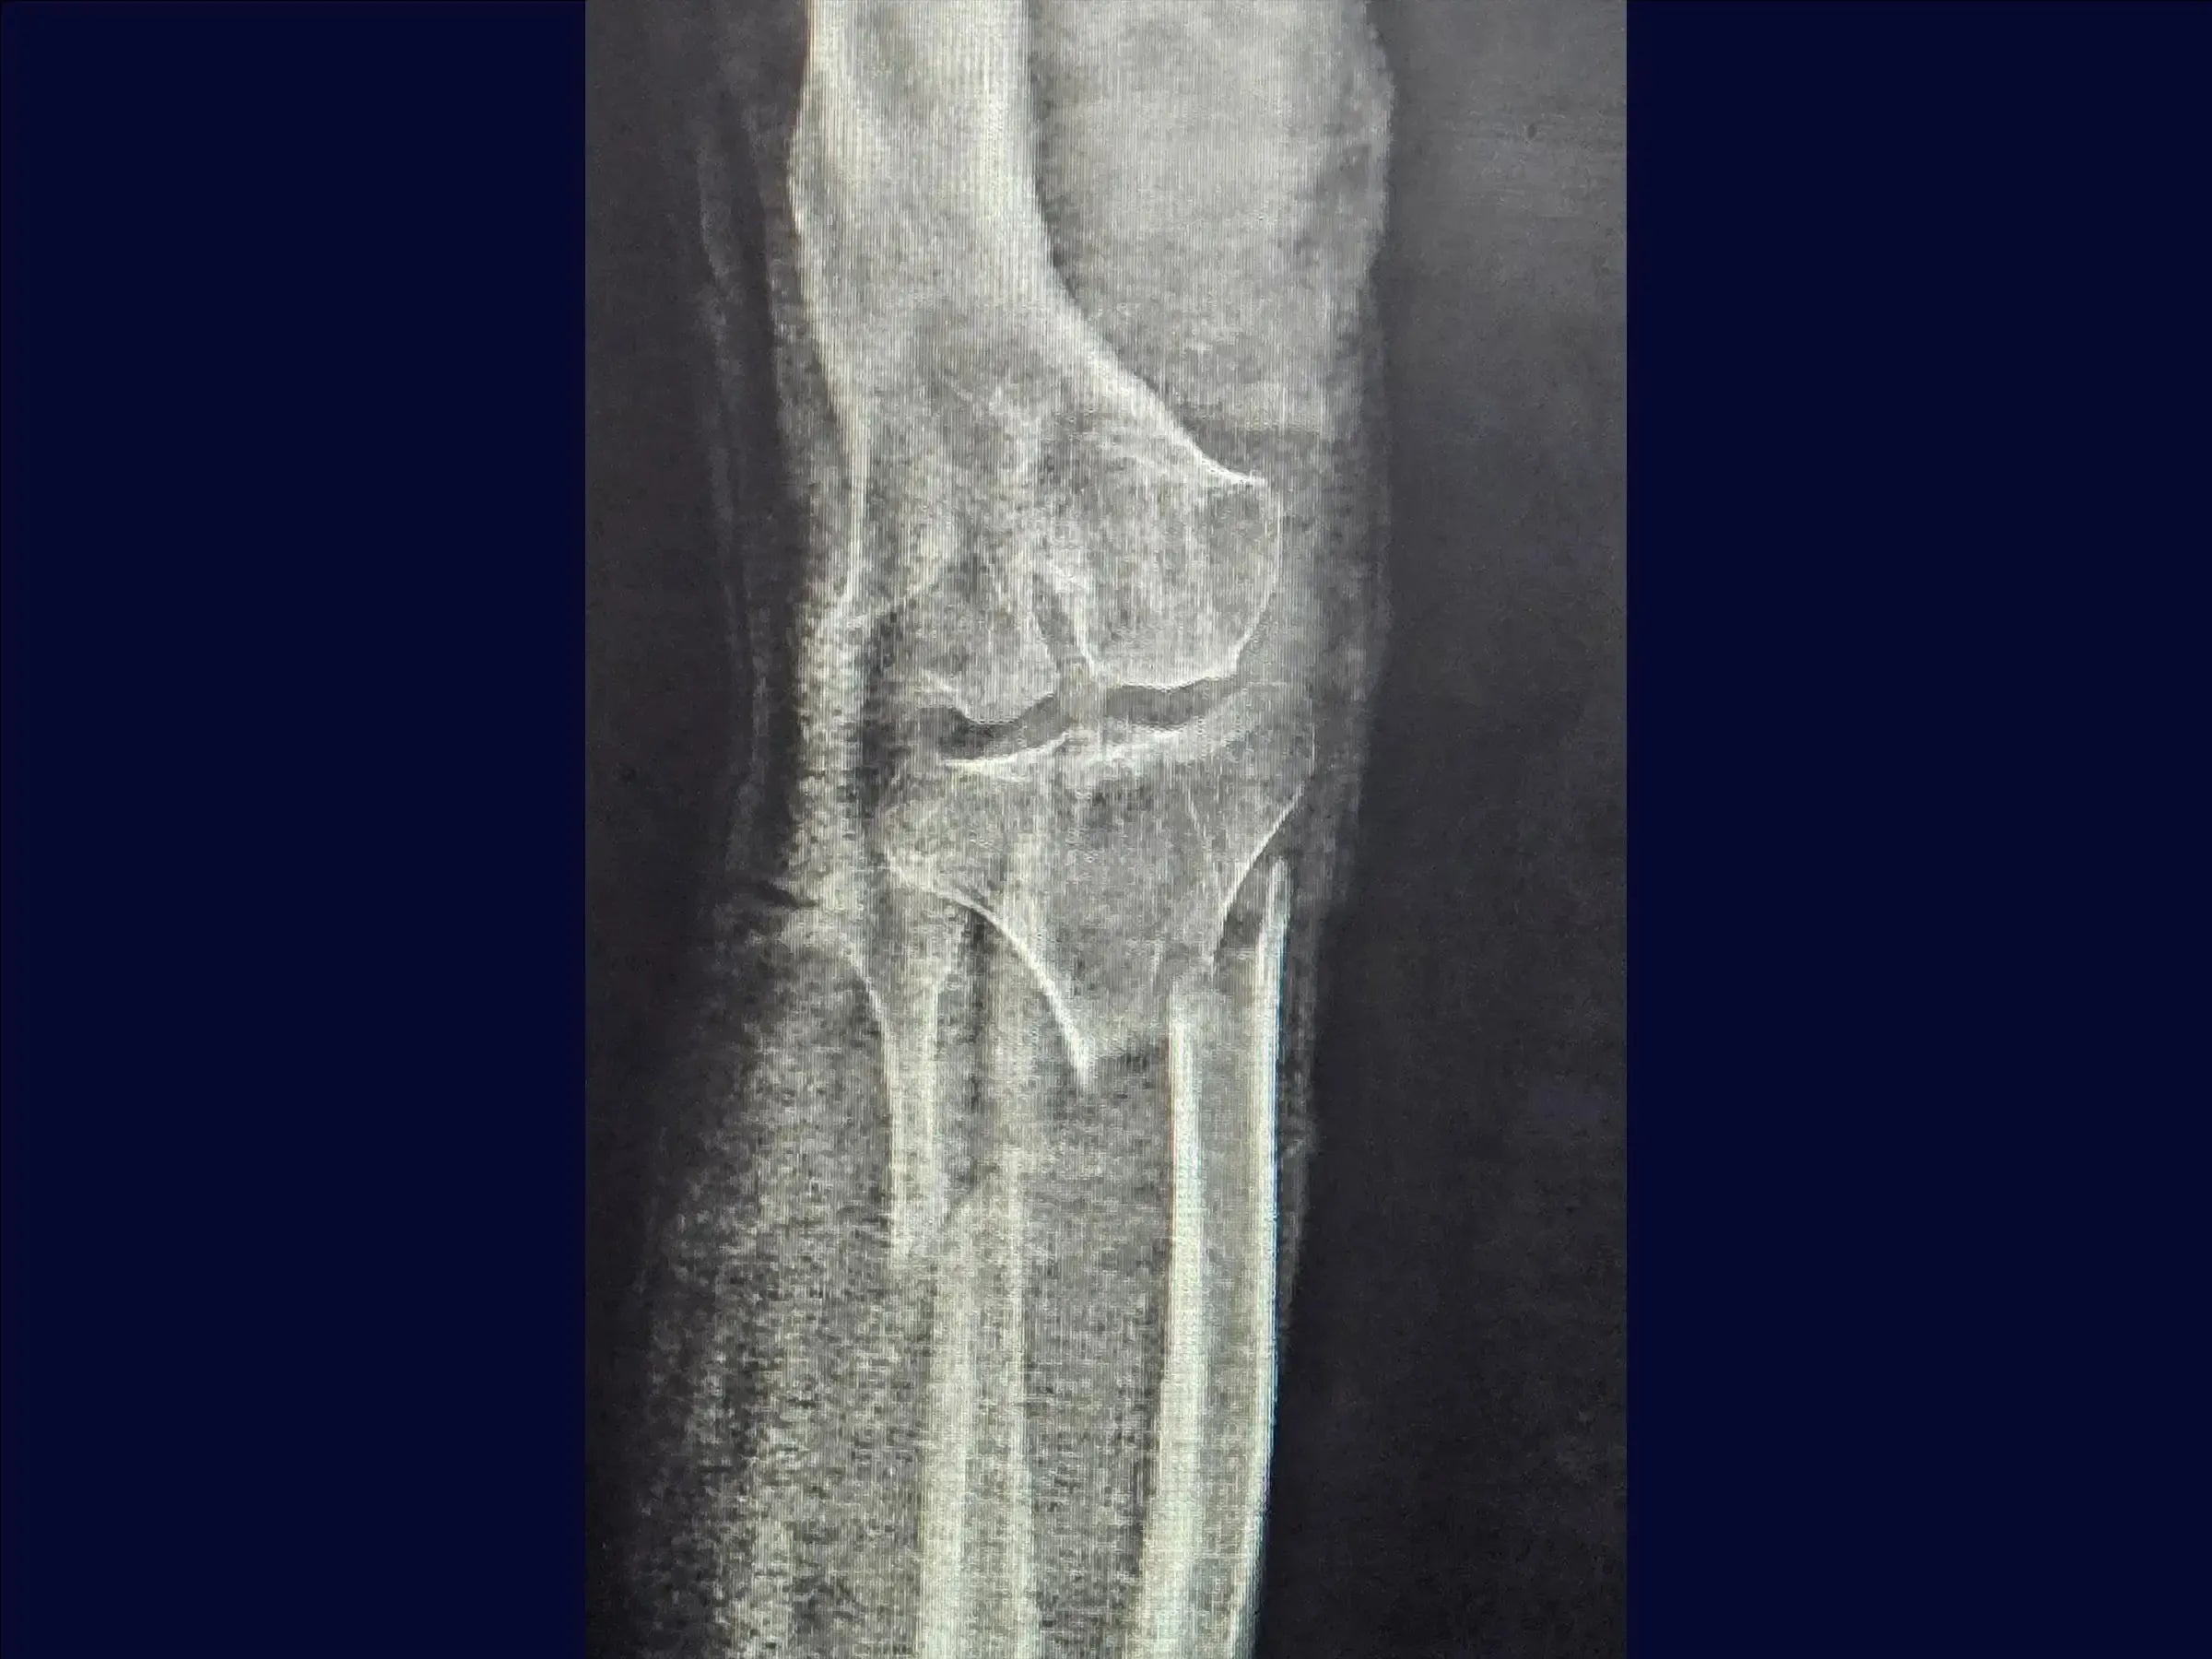

High Diaphyseal Tibia Fracture with Deformity

Fracture treatments diaphyseal tibial shaft fractures with pre-existing bone deformity represent a technical challenge due to the instability of the shear line and the presence of osteopenic bone.

- Preoperative planning with image intensifier.